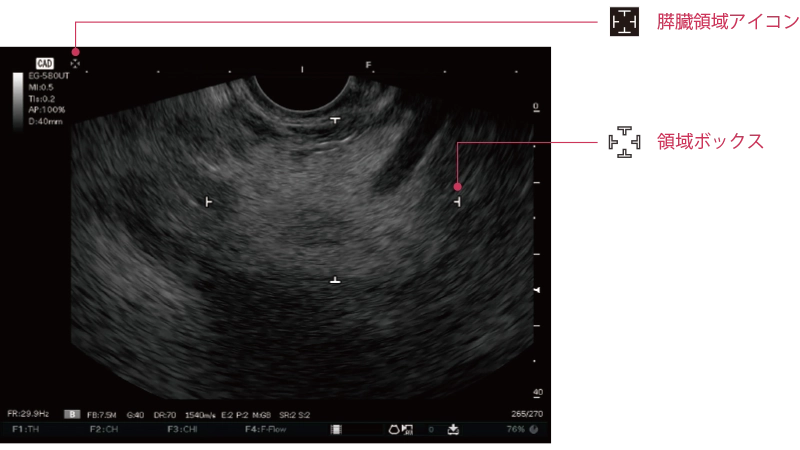

膵臓が存在すると推定される領域を検出し、その結果をリアルタイムにモニターに表示します。

膵臓が存在すると推定される領域を検出し、対象領域の上下左右を白色のマークで囲って表示します。